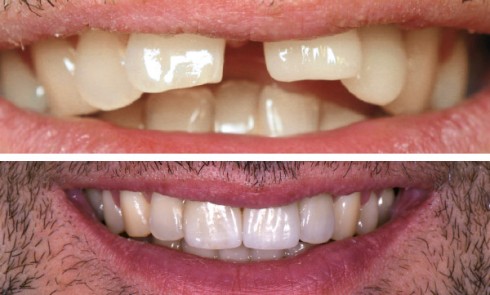

Examen clinique Ce patient est venu dans notre cabinet pour résoudre un problème esthétique vieux de trente ans : une chute...

La demande esthétique des patients ne cesse de progresser et se traduit par une augmentation du nombre de consultations ayant...